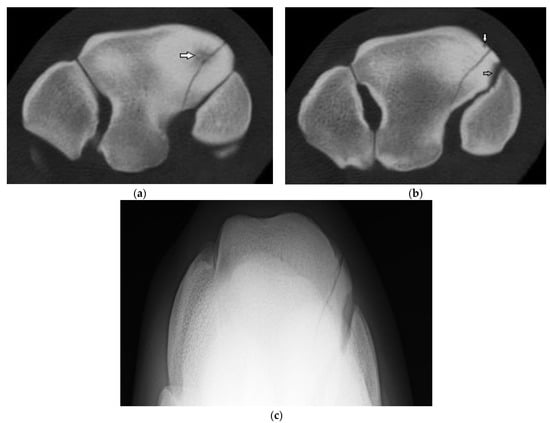

Five horses had a sagittal fracture of the RaF (one incomplete, three complete, and one unsure on DR and CT but determined most likely incomplete); all lacked comminution. In one horse, both observers were unsure whether the incomplete RaF Fx was sagittal or corner on DR; CT confirmed a sagittal Fx. In another horse, both observers were unsure whether the Fx was sagittal or corner and whether the Fx was complete. In both cases, CT confirmed fracture configuration as sagittal and identified additional lesions not identified on radiographs (Supplementary Table S3). Of the three horses with complete sagittal fracture, all had some lysis of the proximal SCB at the fracture margin within the mid RaF (Figure 3) and 2 had additional lesions including DCL and OF not evident radiographically.

Figure 3. Images of the right carpus of a 3-year-old thoroughbred filly. (a) Transverse CT image of the distal row of carpal bones reveal a sagittal slab fracture of the radial facet of the third carpal bone (C3). This slice through proximal C3 reveals a large subchondral lucency within the radial facet that was not evident radiographically. (b) A transverse CT image through mid C3 reveals a partial thickness subchondral lucency at the articulation with the second carpal bone (C2) (arrow) and a small dorsal cortical lucency (white arrow). (c) Flexed dorsoproximal-dorsodistal oblique radiographic view of the distal row of carpal bones. The sagittal fracture and subchondral lucency at the articulation with C2 is evident but the subchondral lucency mid radial facet is not.